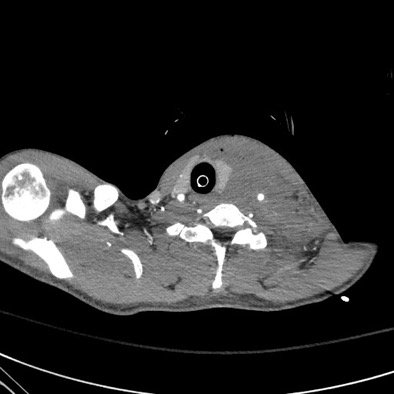

A Case Report of a Transected Carotid Artery Caused by a Stab Wound to the Neck

DOI: https://doi.org/10.21980/J8BP8MThe post intubation chest x-ray (CXR) showed severe rightward displacement of the trachea (purple arrow). The computed tomography angiogram (CTA) showed transection of the left common carotid artery (LCCA), extensive neck hematoma without extravasation and severe tracheal deviation to the right (blue arrow). The intravenous (IV) contrasted chest computed tomography (CT) image showed a lateral contrast projection from the aortic arch at the level of the isthmus (green and pink arrows). There were no other significant injuries reported on the CT scans of the chest, abdomen and pelvis.